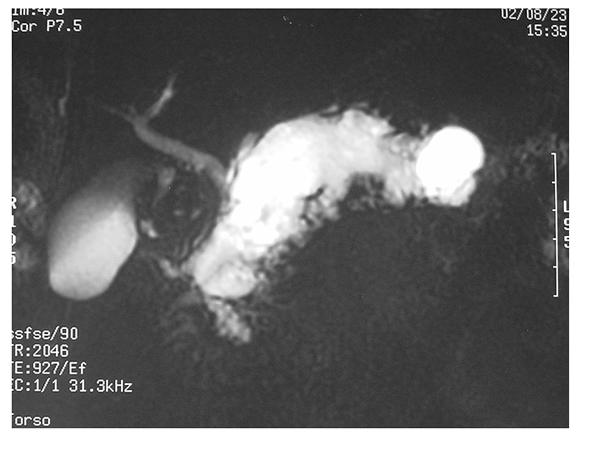

İPMN (İntraduktalPapillerMüsinözNeoplazi)

Son 15 yılda klinikte giderek artan sayıda rastlanılan bir problemdir. Pankreas kanalından gelişen başlangıçta iyi huylu olan polip benzeri kitle pankreas kanalları içerisine müsinöz (sümüksü) bir sıvı salgılar. Bu sıvı ana pankreas kanalının genişlemesine ve yan dallarda kistlerin oluşmasına neden olur. Üç ana tipi vardır. Ana kanal, yan dal ve bunların birleşiminden oluşan miks tip. Ana kanal tipi yüksek pankreas kanseri gelişimi riski nedeniyle tanı konulduğu anda cerrahi adayıdır. Yan dal tipinde kistin çapı, duvarının yapısı, hastanın şikayetleri göz önüne alınarak gözlem veya cerrahi kararı verilir.

İPMN ana kanal tipi %30-70 oranında pankreas kanseri ile birliktedir. İPMN tanısı konduğunda pankreas kanseri varlığını düşündüren faktörler sarılık, yüksek CA 19-9 düzeyi ve pankreasta kitle varlığıdır. Günümüzde yaklaşım pankreas kanseri gelişmeden cerrahi olarak tedavi etmektir. İPMN tanısını koymanın en önemli yanı bu önleyici tedaviyi olanaklı kılmasıdır.

Cerrahi tedavi de ana kanal tipi İPMN varlığında genel olarak Whipple ameliyatı gerekmektedir. Başlangıçta kanser tanısı almayan hastalarda Whipple ameliyatı kararı almak herkes açısından zorluk gösterse de alınan riskler ile elde edilecek faydalar karşılaştırıldığında her zaman cerrahi kararı doğru karar olmaktadır.